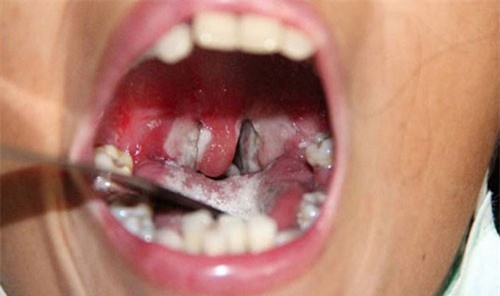

Một ổ dịch bạch hầu vừa được phát hiện tại trường tiểu học ở huyện miền núi Quảng Nam với 7 em học sinh mắc bệnh, trong đó có 1 em tử vong.

Sau khi xuất hiện dịch bệnh bạch hầu bùng phát tại trường cấp 3 trên địa bàn huyện Tây Giang khiến 2 học sinh tử vong. Bộ Y tế đã đưa ra khuyến cáo phòng bệnh bạch hầu gấp.

Sở Y tế Quảng Nam cho biết địa phương này xuất hiện dịch bệnh bạch hầu bùng phát tại trường cấp 3 trên địa bàn huyện Tây Giang khiến 2 học sinh tử vong.

(DNVN) - Ngày 15/7, UBND tỉnh Bình Phước quyết định công bố dịch bệnh bạch hầu quy mô cấp huyện do lo ngại bệnh lan rộng sau khi có 3 người tử vong, hàng chục người nhập viện.

(DNVN) - Chiều 14/7, Sở Y tế tỉnh Bình Phước họp báo thông tin về bệnh bạch hầu và cho biết sẽ tiếp tục tiêm vắcxin cho người dân trong vùng dịch, ưu tiên từ 6-26 tuổi.

(DNVN) - Trước diễn biến của tình hình dịch bệnh bạch hầu tại tỉnh Bình Phước khiến 3 người tử vong, Cục Y tế dự phòng (Bộ Y tế) đã có Công điện gửi Sở Y tế tỉnh Bình Phước để khẩn trương triển khai các biện pháp tăng cường công tác phòng chống dịch bạch hầu.

(DNVN) - Theo PGS.TS.BS Nguyễn Văn Kính, bệnh bạch hầu tử vong chủ yếu do độ tốc bạch hầu gây suy tim, viêm thận và bệnh nhân chết là do các biến chứng này.